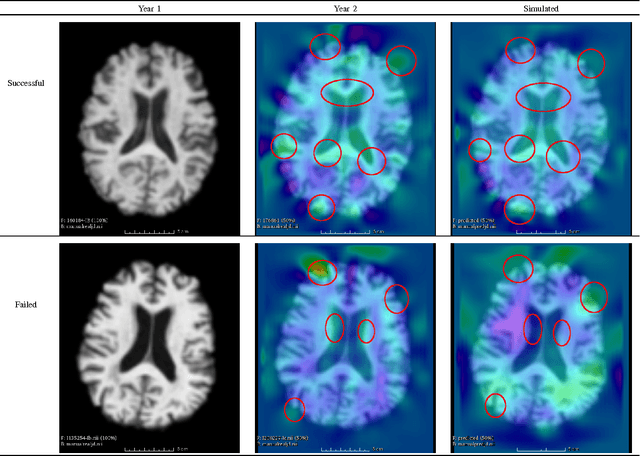

Abstract:We present a longitudinal MR simulation framework which simulates the future neurodegenerative progression by outputting the predicted follow-up MR image and the voxel-based morphometry (VBM) map. This framework expects the patients to have at least 2 historical MR images available. The longitudinal and cross-sectional VBM maps are extracted to measure the affinity between the target subject and the template subjects collected for simulation. Then the follow-up simulation is performed by resampling the latest available target MR image with a weighted sum of non-linear transformations derived from the best-matched templates. The leave-one-out strategy was used to compare different simulation methods. Compared to the state-of-the-art voxel-based method, our proposed morphometry-based simulation achieves better accuracy in most cases.